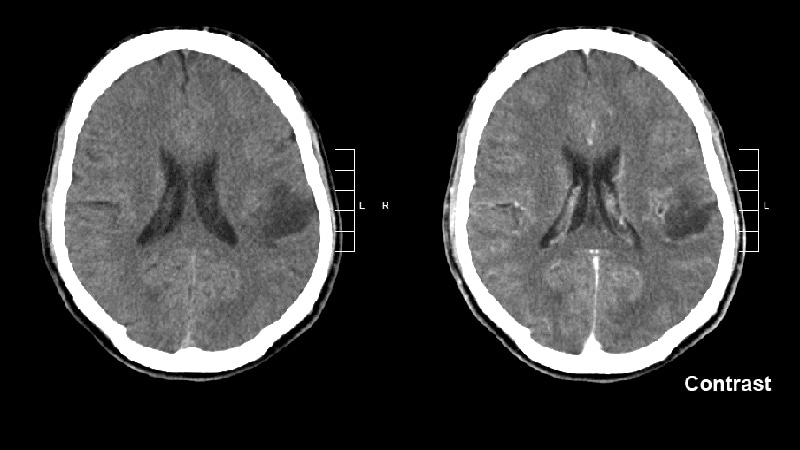

Vorasidenib is an oral inhibitor of the IDH1 and IDH2 enzymes, with the ability to cross the blood–brain barrier. Mutations in IDH1 are found in about 80% of grade 2 gliomas, and IDH2 mutations occur in about 4%.

Many patients with IDH-mutant grade 2 gliomas are initially followed with serial MRI scans, with toxic therapies reserved for use after disease progression, Mellinghoff noted.